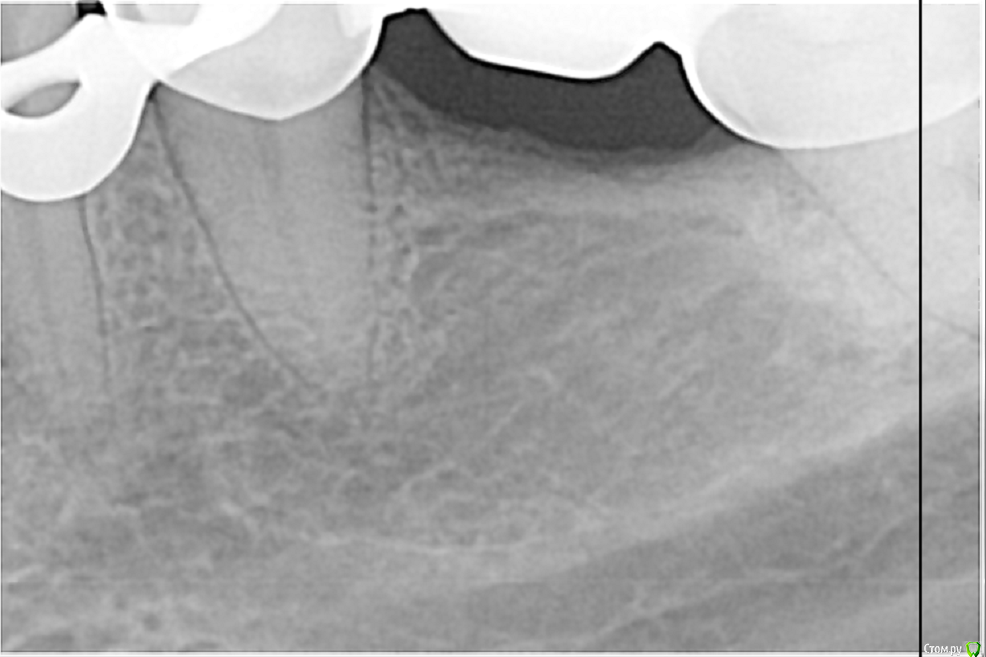

Закон парных случаев в этот летний месяц превзошел себя! Апогеем стал периодонтит 34 с двумя каналонаполнителями, при этом один торчал за апекс. Тут пришлось повозиться, достал через 40 минут. И вроде бы апикальный упор был и мерял-перемерял и всё равно паф.((( Как думаете мастер за апексом? Так как дело было летом, после НГ вызову на контроль и обязательно поделюсь результатом!